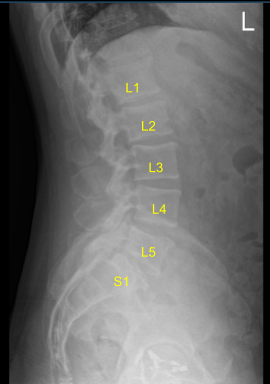

This Patient presented to our outpatient clinic with signs and symptoms of lumbar stenosis and spondylotic radiculopathy as well as epidural lipomatosis. They failed extensively with non surgical treatments, which were unsuccessful in alleviating their symptoms. Imaging demonstrated the above mentioned issue.

Spinal needle and fluoroscopy were used to localize the L5-S1 level. A midline incision was demarcated. Skin was sterilized with DuraPrep. Sterile drapes were placed in usual manner. 1% lidocaine with epinephrine was infused.

Skin was opened with #10 blade scalpel. Hemostasis was obtained with bipolar. Bovie monopolar and Cobb elevators were used to carry the incision down, incising the fascia and performing subperiosteal dissection exposing the L4, L5 and S1. Self-retaining retractors were placed. A Woodson elevator was placed under the L4 lamina. C-arm unit, which was draped sterilely, was brought into the field and used to confirm the level.